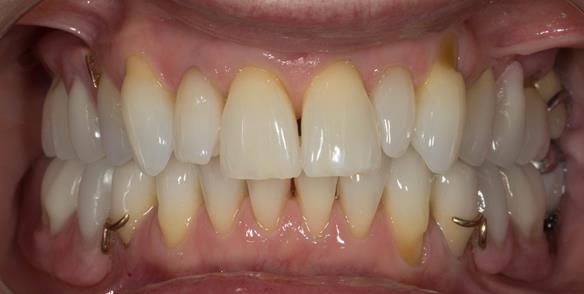

This newsletter describes in step by step detail Angela's transition through immediate partial dentures to crown supported definitive metal based dentures.

This 58 year old woman was referred to me by her general dental practitoner for treatment.

- Generalised Periodontitis; Stage 4, Grade C, Currently Unstable. Risk Factors: Type 1 diabetes. 16, 17 - hopeless prognosis. 14, 24, 26, 27, 34, 37, 44 - guarded prognosis

- Poor marginal fit and poor appearance of crowns and bridgework

- Yellowing teeth

The clinical situation and treatment process is shown in detail below with photographs. I (Finlay Sutton) provided the clinical work and Rowan Garstang provided the technical work.